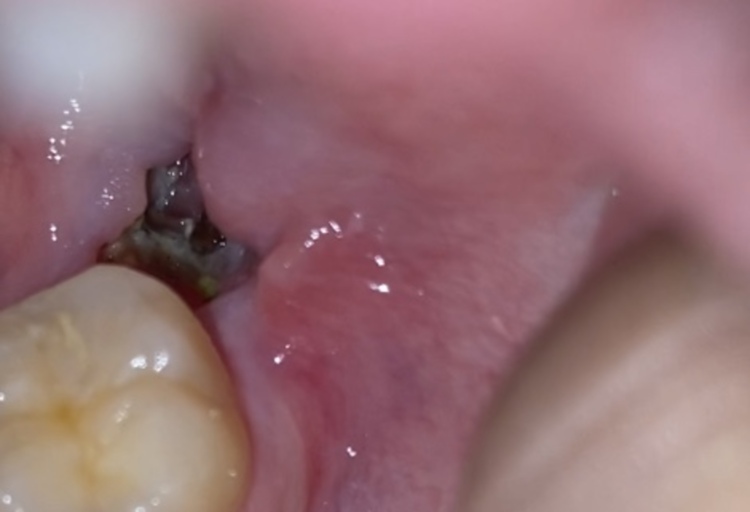

Hey there, I've recently taken out my wisdom tooth, (this is day 2) and took a picture of it. It was white, and im wondering if thats what it is supposed to look like. Lastly, there is a pimple-like structure to where the doctor injected the local anesthesia, is that normal? (PS I've attached a photo of what my inside mouth looks like atm, sorry if it's graphic.)

From the picture, everything looks like it is healing well. If you are not already, start rinsing with warm salt water 2-3 times daily. This is very therapeutic to the tissues and will help keep the area free from debris. The structure you are speaking of near the injection site is more than likely a salivary glad or an irritation from the injection. If it does not resolve on its own within the next 3-5 days, it would be a good idea to have the treating dentist re-examine the area.